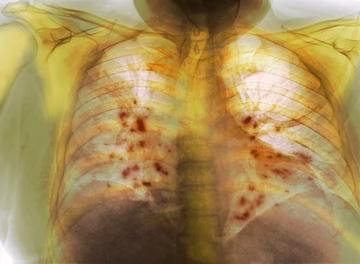

Kovid pluća s vakcinom i bez primljene vakcine FOTO

Pogledajte kako izgledaju pluća zahvaćena koronom